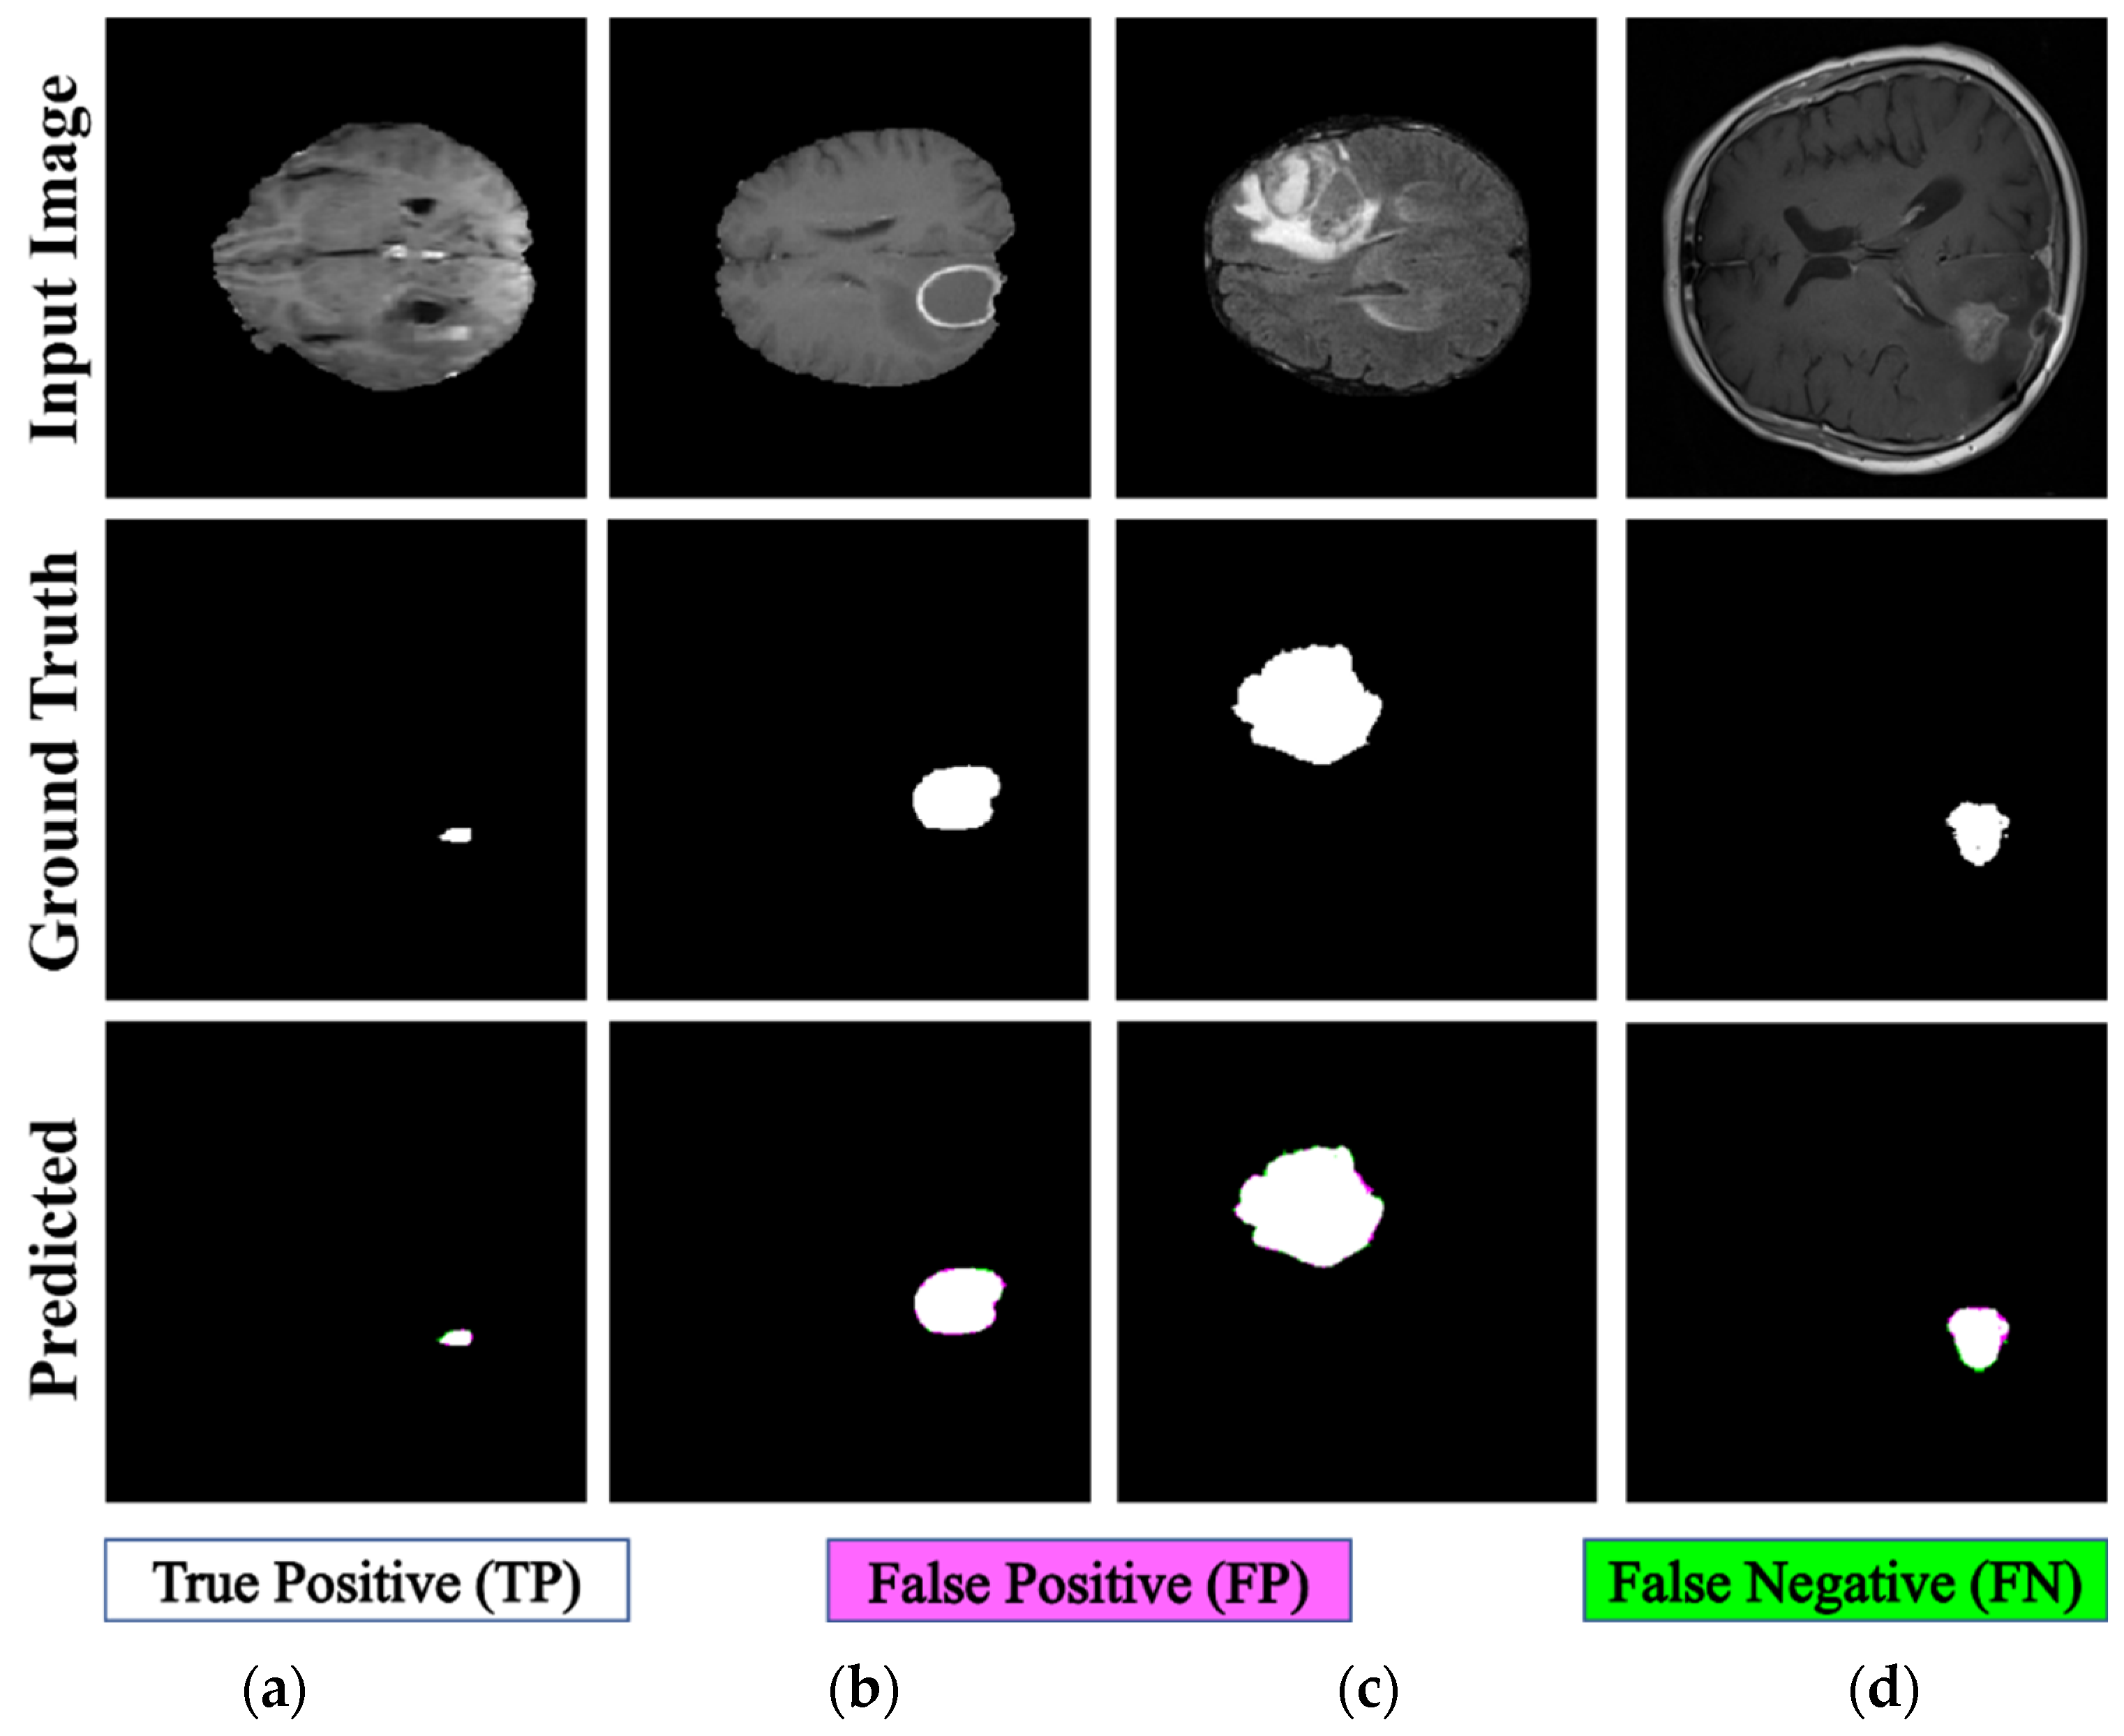

To analyze heterogeneous datasets, the PFA-Net trained on Dataset-1 was applied to the entire Dataset-2 for testing. This dataset contained the MRI scans of 20 patients diagnosed with primary glioblastoma. Each patient’s data comprised two MRI examinations, totaling 8798 scans. Examples from Dataset-2 are shown in Figure 5.

Figure 5.

Examples of brain tumor scans in the first row, with corresponding segmentation masks in the second row from Dataset-2.

4.5. Testing Results of Heterogeneous Dataset Analysis

We performed a comprehensive comparative analysis of the performance of PFA-Net, an automated diagnostic screening method for heterogeneous dataset analysis, in relation to various recent CAD methods, as presented in Table 2 and Table 12. A previous method [19] used a pre-processing step to enhance the performance of the heterogeneous dataset analysis. Some methods [63] do not consider a complete heterogeneous dataset analysis. Our proposed PFA-Net demonstrates superior performance compared with previous methods for the analysis of a completely heterogeneous dataset without requiring a pre-processing technique.

Table 12 presents a comparison of the performance of PFA-Net in relation to various state-of-the-art methods [18,19,44,66,76,77,78,79] for analyzing the heterogeneous dataset. The proposed method outperforms the second-ranked method [19] with DS and IoU performance gains of 64.58% and 59.03%, respectively, as listed in Table 12. Additionally, our method is efficient in terms of the number of parameters, testing elapsed time, and memory usage compared to the second-best method [19], as shown in Table 12. Specifically, the parameters of the proposed PFA-Net are 19.49 M less than those of MDFU-Net (i.e., 31.48 M [Proposed] << 50.97 M [MDFU-Net]). The average processing time of one BT scan is 0.77 s less than that of MDFU-Net (i.e., 1.53 s [Proposed] < 2.3 s [MDFU-Net]), and the average memory used by the proposed PFA-Net is 219.11 megabytes (MB) less than that of MDFU-Net (i.e., 318.69 MB [Proposed] << 537.8 MB [MDFU-Net]), as shown in Table 12. However, the computational complexity of the proposed PFA-Net is high in terms of gigaflops floating-point operations per second (GFLOPS) compared to the second-best method [19] (i.e., 126.85 GFLOPS [Proposed] > 105.85 GFLOPS [MDFU-Net]). This complexity is attributed to the intensive computations required for parallel feature extraction by the novel PFA block. Nevertheless, the proposed PFA-Net ranked first in terms of segmentation accuracy compared to all other methods, as indicated in Table 12. Figure 10 shows the qualitative results obtained using the proposed PFA-Net on a heterogeneous dataset.

Figure 10.

Qualitative results of proposed PFA-Net for heterogeneous dataset analysis.